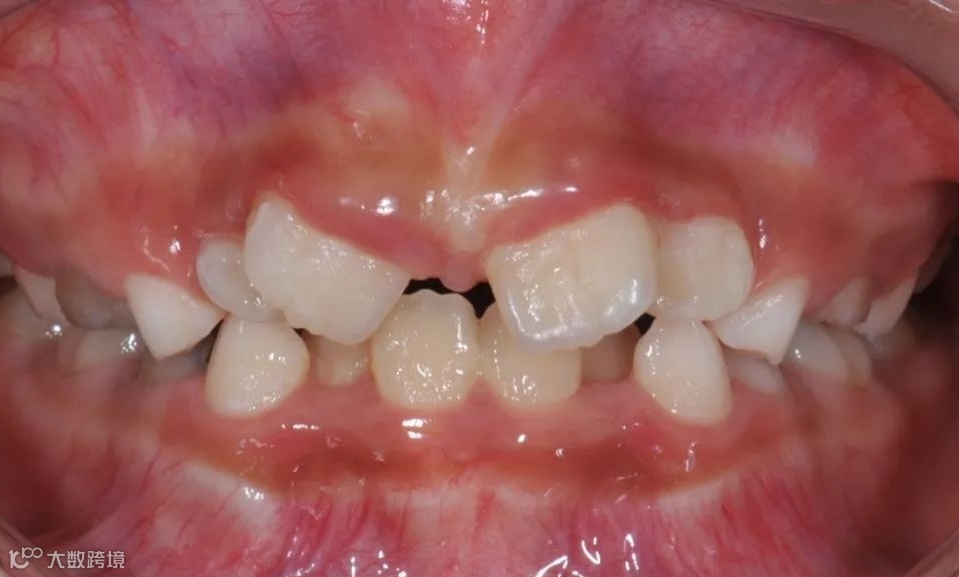

替牙期牙性反𬌗治疗前

替牙期牙性反𬌗治疗后